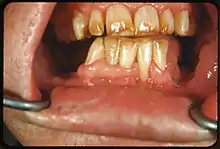

Tooth discoloration is abnormal tooth color, hue or translucency.[1] External discoloration is accumulation of stains on the tooth surface. Internal discoloration is due to absorption of pigment particles into tooth structure.[2][3] Sometimes there are several different co-existent factors responsible for discoloration.[4]

Extrinsic discoloration

Extrinsic discolorations are common and have many different causes.[10] The same range of factors are capable of staining the surface of restorations (e.g., composite fillings, porcelain crowns).[10] Some extrinsic discolorations that are allowed to remain for a long time may become intrinsic.[11]

- Tobacco: Tar in smoke from tobacco products (and also smokeless tobacco products) tends to form a yellow-brown-black stain around the necks of the teeth above the gumline.[12]